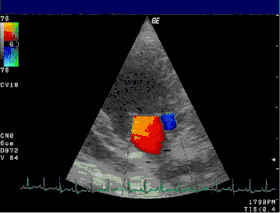

Echocardiogram

![]() |

| Severe MR | Legend |

| 1 Left atrium (LA) – 2 MR Jet, LV Left ventricle – RV Right ventricle – RA Right atrium | |

An echocardiogram is commonly used to confirm the diagnosis of MR.[16] Color doppler flow on the transthoracic echocardiogram (TTE) will reveal a jet of blood flowing from the left ventricle into the left atrium during ventricular systole. Also, it may detect a dilated left atrium and ventricle and decreased left ventricular function.[6] A transesophageal echocardiogram can give clearer images if needed as the back of the heart can also be viewed.[17]